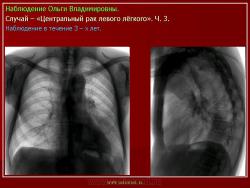

Наблюдения коллег.